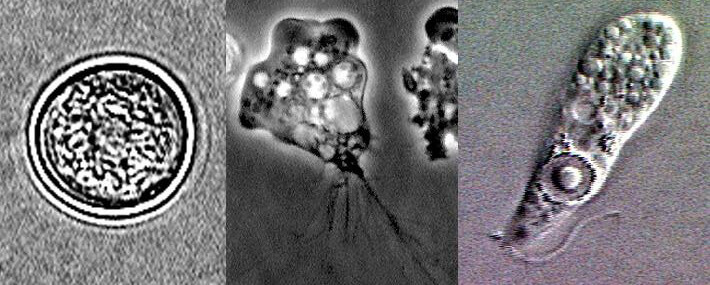

El nombre oficial de esta ameba es Naegleria Fowleri. Pertenece a los protozoos de vida libre por su capacidad de sobrevivir y replicarse en el ambiente sin necesidad de un hospedador. Fowler y Carter fueron los primeros en registrar el primer caso de meningoencefalitis amebiana primaria (MAP) en 1965 producida por la Naegleria Fowleri.